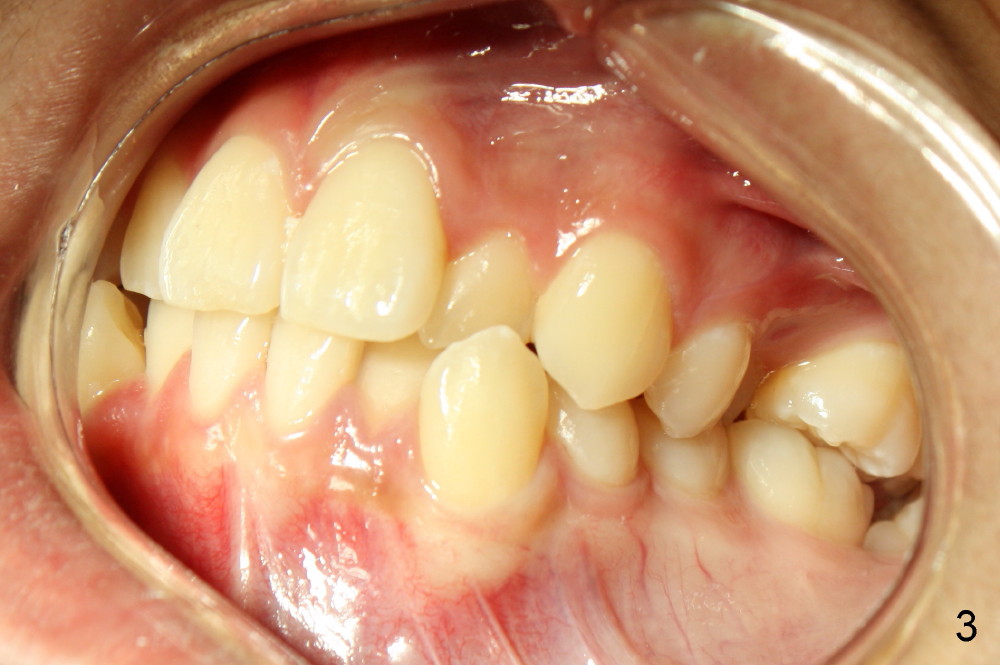

A 13-year-old boy has severe crowding (Fig.1-5). Four of the first bicuspids were extracted on 02/17/2014. Full mouth brackets or bands (except #18) were placed on 03/27/2014. Alignment improved 2 months later (Fig.11, 05/24/2014). The upper 18 ss wire was modified (Fig.12), and fixed with alastiks (Fig.13,14). One month later (07/01/2014), local alignment also improved (Fig.15); the upper modification is confined to one tooth.

Four and a half months post bracketing (Fig.21-25), what do you find and what should be done next?